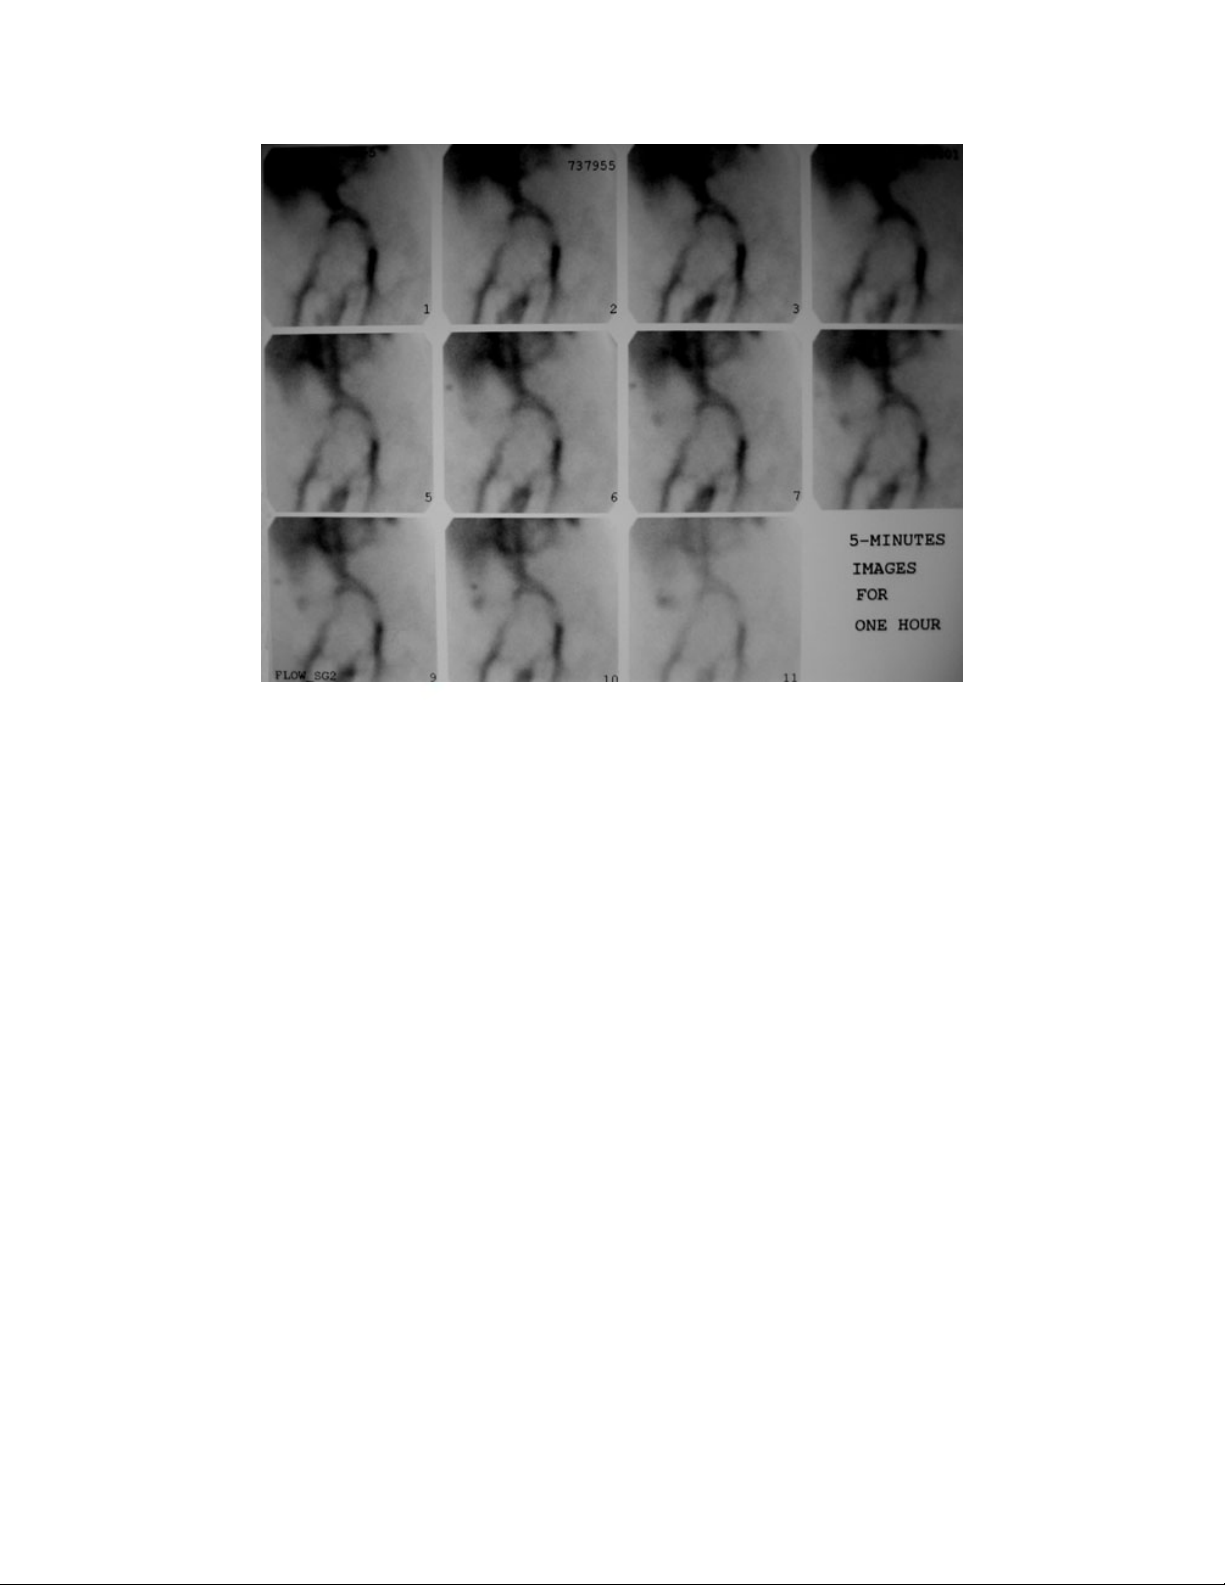

Endoscopy for upper gastrointestinal bleeding and scintigraphy for lower

gastrointestinal bleeding are important steps in the management and outcome of

transcatheter angiography. Computerized tomography angiography is a promising

tool for the treatment of both upper and lower GI bleeding, and this procedure has

become part of the imaging toolset. In addition, angiography performed outside of

working hours had a higher rate of clinical success than the angiographies

performed in working hours, most likely secondary to much appropriate timing of

arteriogram in terms of critical bleeding intervals.